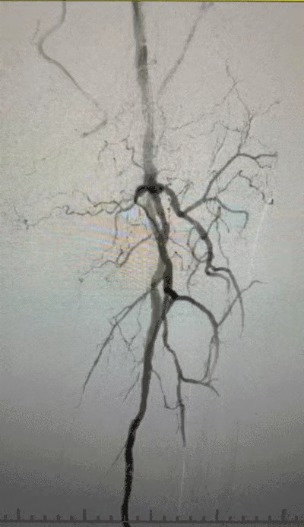

· Badanie fizykalne: słabe pulsy udowe; brak pulsów podkolanowych i grzbietu pedis; owrzodzenie lewego pierwszego palca; martwica prawego pierwszego i drugiego palca

· Obrazowanie przedoperacyjne: Ciężkie, rozproszone zwapniałe zwężenie w obustronnych tętnicach kończyn dolnych

Biorąc pod uwagę złożony stan naczyniowy, wybraliśmy system cewnika dylatacji balonowej ThorCrack Peripheral IVL. Ze względu na ograniczoną tolerancję pacjenta wykonano etapowe zabiegi interwencyjne na obu kończynach dolnych.

Wynik chirurgiczny

Po zabiegu znacznie poprawiło się zwężenie tętnic, zwiększył się przepływ krwi i wzrosła temperatura skóry. Nie wystąpiły powikłania pooperacyjne. Zarówno pacjent, jak i zespół chirurgiczny byli bardzo zadowoleni z wyników.